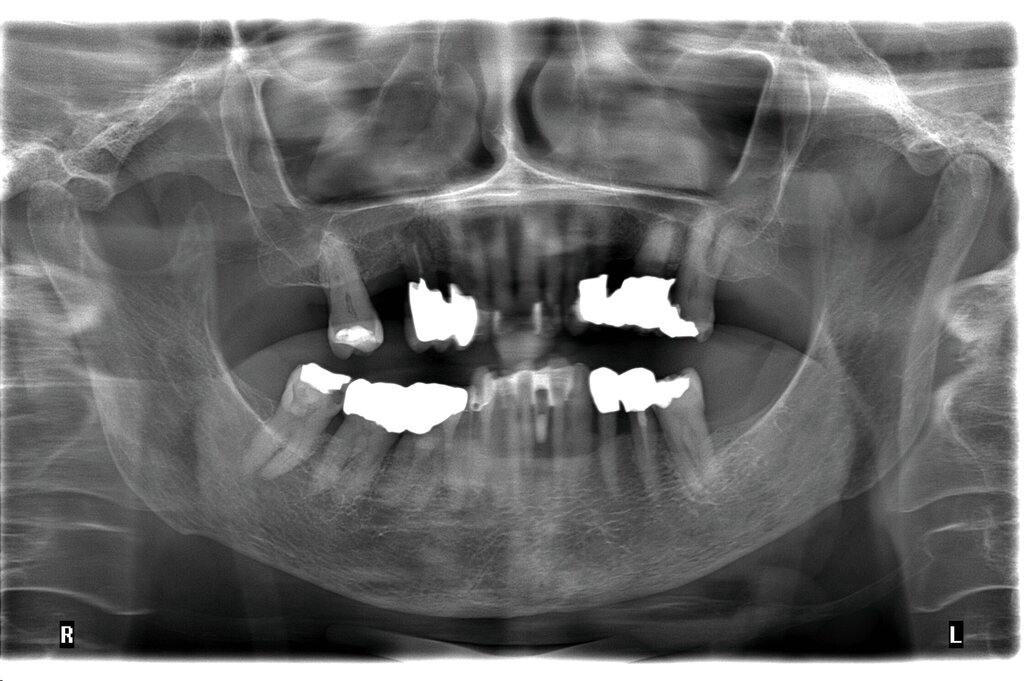

Da anhand eines Zahnfilms festgestellt worden war, dass der Zahn 31 – vermutlich aufgrund einer Paro-Endo-Läsion – eine apikale Aufhellung zeigte, war bereits die Extraktion mit anschließender Umarbeitung und adhäsiver Wiedereingliederung des extrahierten Zahnes als Option angesprochen worden. Kurz vor dem vereinbarten Eingriff meldete sich die Patientin telefonisch, um sich zu erkundigen, ob sie den Termin denn überhaupt noch benötige, da der betroffene, gelockerte Zahn 31 in der Unterkieferfront beim Essen von selbst herausgefallen sei und sie ihn bereits entsorgt habe. Schmerzen, eine Schwellung oder Nachblutungen verneinte die Patientin. Sie wurde gebeten, den vereinbarten Termin am Folgetag dennoch wahrzunehmen, mindestens zur Kontrolle der Wunde, gegebenenfalls zur Planung der Weiterversorgung (Abbildungen 5 und 6).